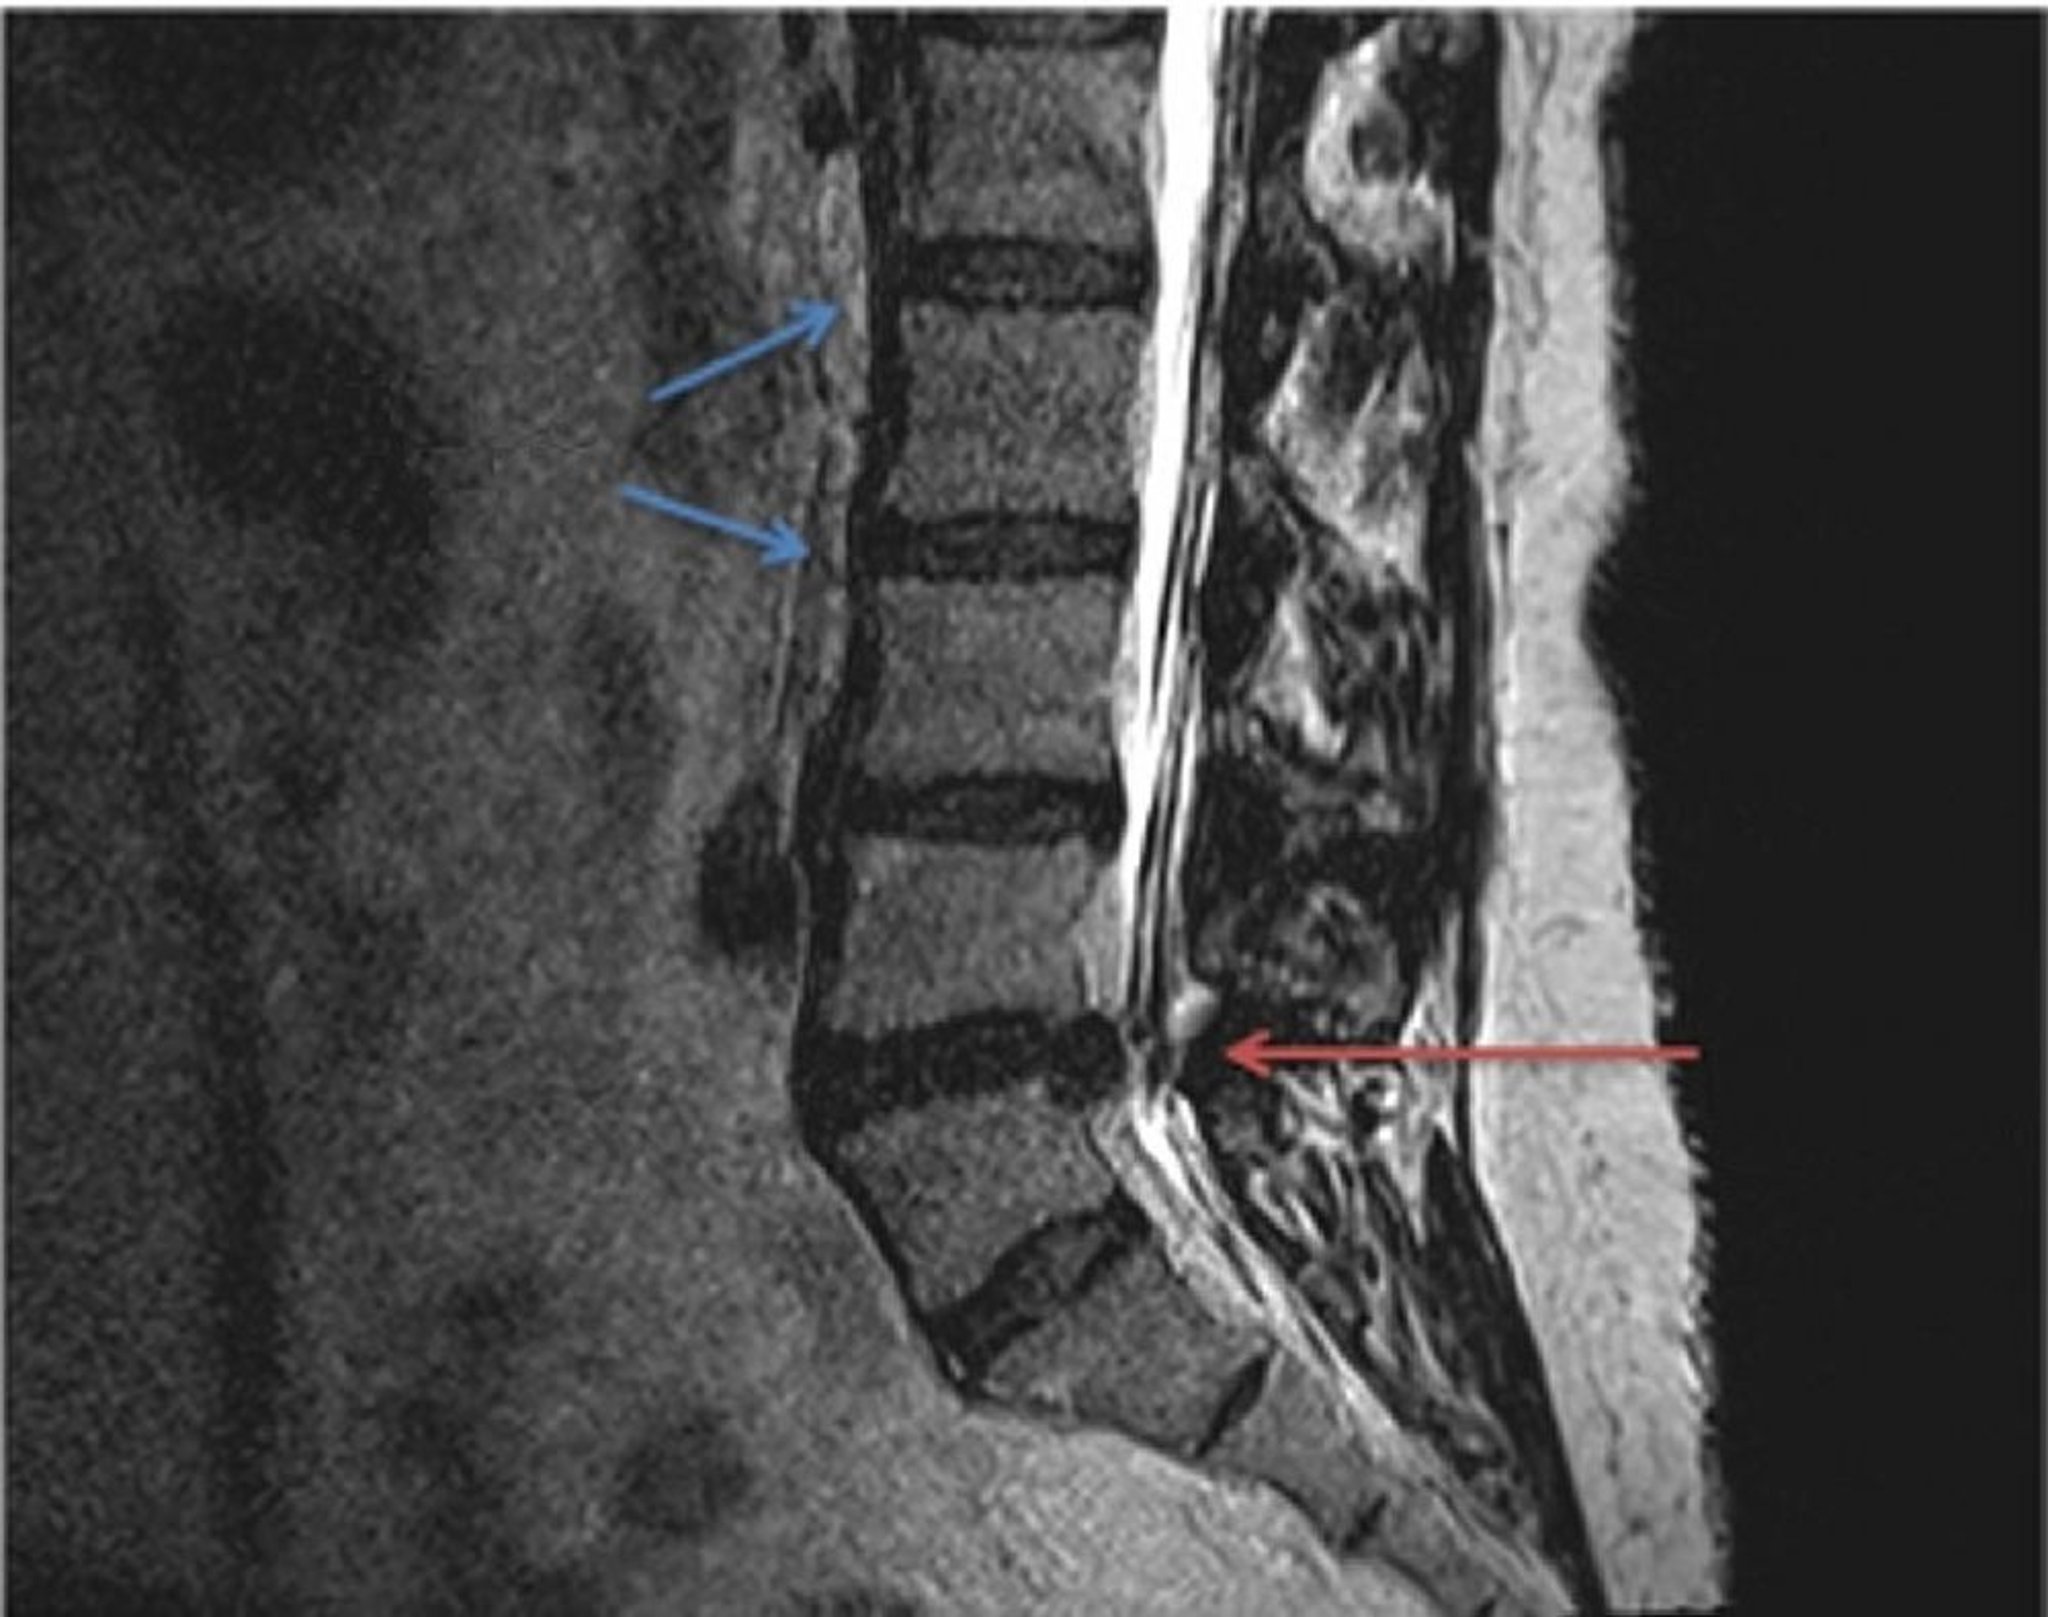

Hernia de disco (RM)

Comparación de la anatomía de los discos lumbares normales (flechas azules) y herniados en una imagen de RM ponderada-T2. La hernia de disco, que se encuentra entre las vértebras L4 y L5 (flecha roja), comprime el nervio espinal que se extiende desde la médula espinal, dando como resultado presión y dolor localizado o radiante.